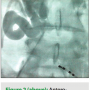

He was taken to the EP laboratory for an electrophysiology study (EPS) and radiofrequency ablation (RFA). Bilateral femoral venous access was obtained without complications. Attempts were made to advance a quadripolar catheter from the right and left femoral veins. However, on both occasions, the catheter could not be advanced through the inferior vena cava (IVC). Thereafter, attempts were made to advance a hydrophilic guidewire into the IVC. At the same site, resistance was encountered. Venography was performed, and intravenous contrast demonstrated complete IVC occlusion with the presence of significant collateralization (Figure 2). As a result, venous access from the lower extremities was abandoned. Given the significant nature of the patient’s symptoms and the importance of performing a curative procedure, we did not wish to abandon the procedure. The right internal jugular vein was then accessed in order to advance the coronary sinus and right ventricular apical catheters. A diagnostic EPS was performed, which resulted in the induction of a supraventricular tachycardia. In the tachycardia, there was evidence of eccentric VA conduction with the earliest atrial activation in the distal coronary sinus, consistent with a left-sided bypass tract. The right femoral artery was accessed without complication in order to perform a left lateral accessory pathway ablation via a retrograde arterial approach. Two lesions resulted in a successful ablation. As a result, the patient underwent a safe and successful RFA in spite of complete IVC occlusion.